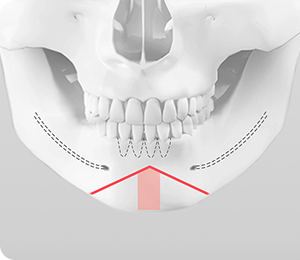

• 기존의 턱끝 수술 방법인 T 절골술은 턱끝의 길이를 조절할 수 없으며, 수술 후 턱끝이 너무 넓은 U 자형이 됩니다. 그리고 절골선이 신경과 치아뿌리에 가까워 신경이나 치아 손상의 위험이 높습니다.

2009년 김태규 대표원장은 기존의 T절골술의 단점과 한계점을 개선한 ㅅ절골술을 직접 개발하였으며, 이는 국제 학술지 The Journal of Plastic and Reconstructive Surgery (PRS)에 논문을 발표하며, 국제 성형외과 학회에서도 여러 차례 발표하여 학술상을 수상하였습니다.

ㅅ절골술은 턱끝의 길이를 조절하여 길게 하거나 짧게 줄일 수 있으며, 무턱이나 주걱턱을 보형물이나 뼈 이식 없이 효과적으로 개선할 수 있습니다. 또한 동시에 비대칭이 심하거나 넓은 턱끝도 부드러운 V라인 턱끝을 만들 수 있으며, 턱끝 신경과 치아뿌리를 피해 절골하기 때문에 신경과 치아 손상없이 안전하게 수술할 수 있습니다.